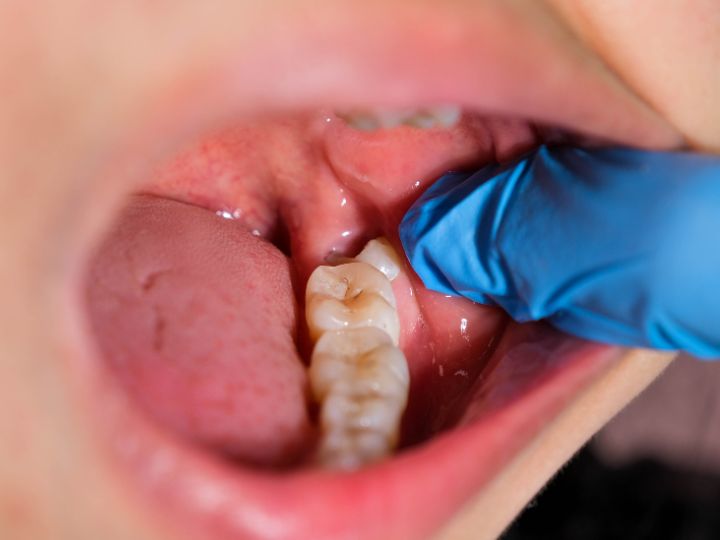

El primer paso en el diagnóstico de las muelas del juicio implica un examen dental completo. Durante este examen, el dentista examinará la boca del paciente, incluyendo la mandíbula y las encías, en busca de signos de problemas potenciales, como enrojecimiento, hinchazón, sensibilidad o presencia de abscesos.

Una vez que el área está completamente adormecida, se realiza una pequeña incisión en la encía sobre la muela que se va a extraer. Esta incisión permite acceder al diente y al tejido circundante para facilitar su extracción.

En algunos casos, especialmente cuando la muela está parcial o totalmente cubierta por encía o hueso, puede ser necesario retirar parte de este para facilitar su extracción.